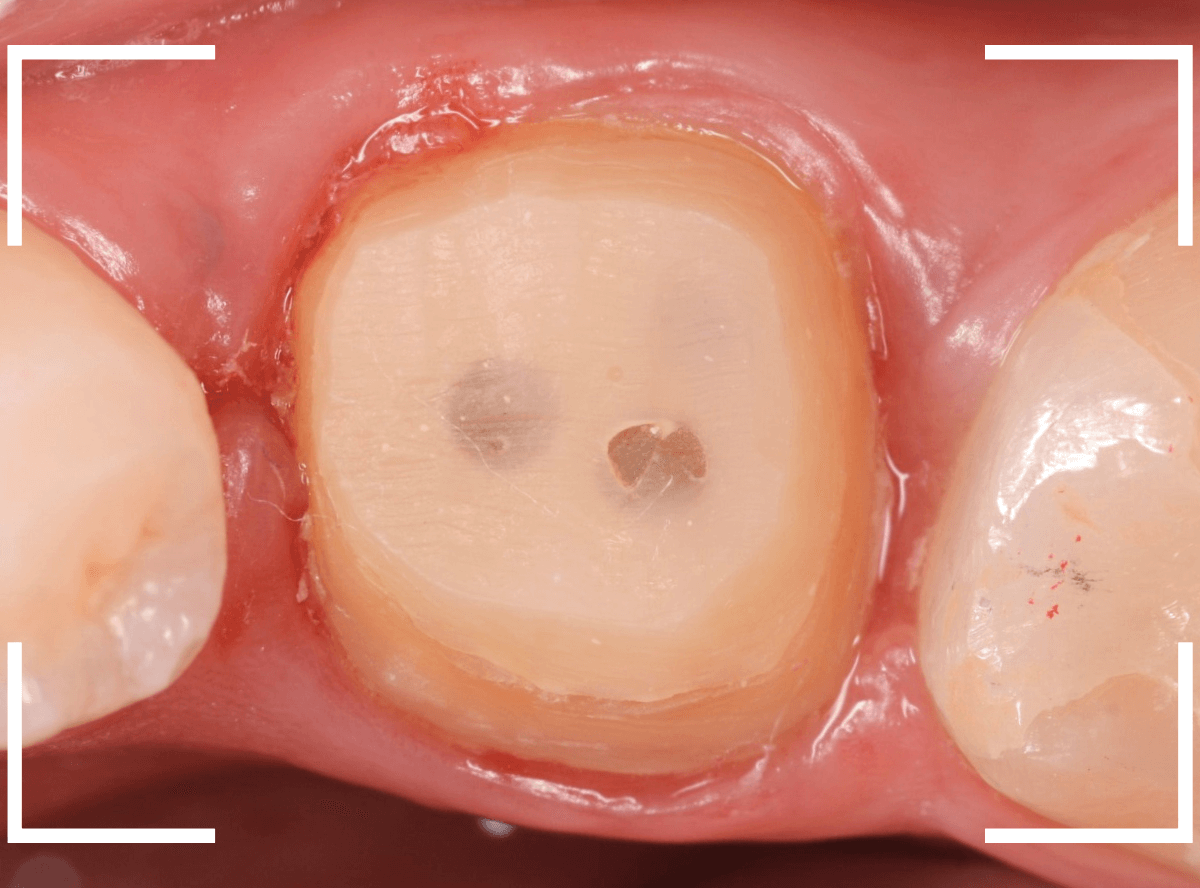

Case.19 メタル・クラウン、除去・再治療後、オール・ジルコニア・クラウンへ 4

今回は、上の奥歯の銀歯(メタル・クラウン)の中で虫歯になってしまった方です。

通常は、さし歯の中が虫歯になってしまうと、レントゲンにも写らず見つけづらいのですが・・・。

歯を裏側から見たところです。

幸い、見える部分に虫歯が

さし歯と歯肉の間に虫歯ができているのがわかります。

歯の奥まで虫歯が進んでいるのか、浅い虫歯ですんでいるのかは治療をしながら調べていく必要があります。